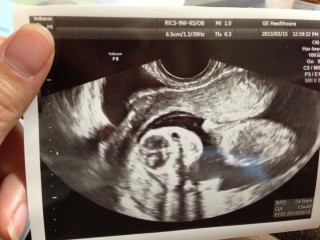

出血してお腹も痛くなってきて、日曜日だったけど病院に電話をして見てもらいに行きました。前回流産をしてるので泣きそうになりながら 診察台へ。ながい沈黙あと‥赤ちゃん元気ですよ!!との言葉を聞いて涙がでました。エコーを見せてもらうと、ガッツポーズをしたあと手を振ってるように見えました(*^^*)赤ちゃんも頑張ってるんだね。生きててくれてありがとう。

指しゃぶりをパパラッチに狙われたようなポーズです(笑)